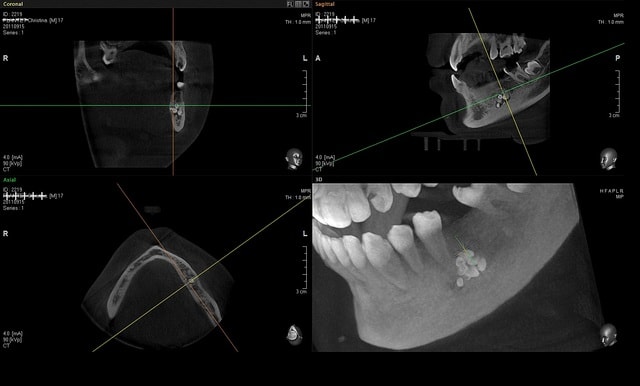

j' ai des coupes de chez morita

dés que je peux j'en mets de vatech

Capture morita 2 stjceh - Eugenol

Capture morita x66gah - Eugenol

Coupes morita fffknv - Eugenol